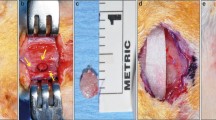

All animals were anesthetized with 50% ketamine (Ketamidor®, Richter Pharma AG, Wels, Austria) and 50% xylazine (Xilagesic®, Laboratories Calier S.A., Barcelona, Spain), administered by intraperitoneal injection at a dose of 0.1 mL/100 g body weight. When general anesthesia was achieved, local anesthesia of the mandibular symphysis was reinforced using articaine hydrochloride 4% with 1:100.000 epinephrine (Septodont, Saint-Maur-des-Fossés, France), achieving a local vasoconstrictor effect to reduce surgical bleeding. The submandibular region was shaved, washed with physiological serum, and covered with a 10% povidone-iodine solution. A 10-mm-long incision (crescent-shaped, curving caudally) was made at the lower edge of the mandible (Fig. 2A). The skin was elevated to expose the periosteum. An additional incision was made in the periosteum to expose the mandibular symphysis completely. Lastly, the fibrous tissues between the left and right mandibles were curetted, exposing the natural CSBD. The mean dimension of this defect in an adult 15-week-old female SD rat with an approximate weight of 250 g is 2 × 4 mm [24].

Creating and filling the CSBDs in the mandibular symphysis. A A 10-mm-long incision (crescent-shaped curving caudally) was made at the lower edge of the mandible. B Filling CSBDs (2 × 4 mm) in an osteoporotic animal with 10 mg porous BC cultured with 7.5 × 105 BFPSCs with osteogenic induction. C Suturing the periosteum. D Suturing the skin

The CSBDs in the mandibular symphyses of eight animals in each group were filled with 10 mg porous BC Osteosynt@ (Eincobio Biomaterial Ltd., Belo Horizonte, MG, Brazil) (60% HA/40% β-TCP), while the CSBDs in the remaining eight animals were filled with 10 mg porous BC Osteosynt@ (Eincobio Biomaterial Ltd., Belo Horizonte, MG, Brazil) cultured with 7.5 × 105 BFPSCs with osteogenic induction (Fig. 2B), according to the amount of BC and the number of BFPSCs proposed by Yagyuu et al. [31]. Planes were closed using 4/0 absorbable sutures (Laboratories Normon S.A., Madrid, Spain) to suture the periosteum (Fig. 2C) and the skin was sutured with braided silk (Lorca Marín S.A., Murcia, Spain) (Fig. 2D).